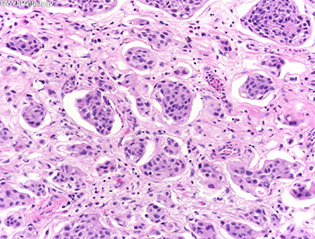

Micro: Composed of cuboidal cells with tubulo-cystic and papillary growth pattern. Scant cytoplasm

- lined by single layer columnar or cuboidal hobnail or flattened cells

- Minimal nuclear atypia and mitotic activity. In contrast, clear cell carcinomas have solid and diffuse growth pattern, ample portions of clear cytoplasm (positive for glycogen on PAS stain), significant

nuclear atypia and increased mitotic activity.

IHC: (+) PAX8, P504 (AMACR)

Px: may recur, but malignant transformation has not been seen

Nephrogenic Adenoma